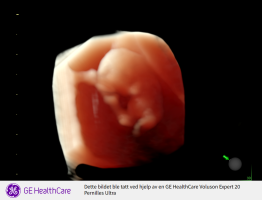

Ååh så herlig med 3D! Perfekt mini menneske